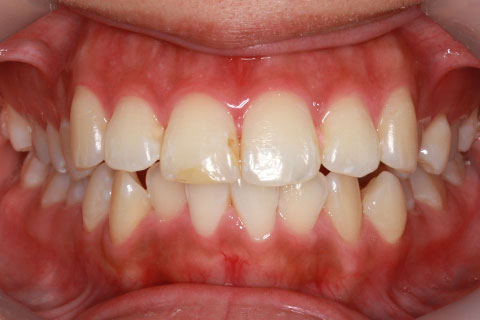

治療前

治療中(開始直後)

治療中(開始半年後)

治療後

- 年齢・性別

- 25歳女性

- 治療期間

- 2年0ヶ月

- 抜歯

- 上下4番抜歯

- 治療費

- 110万円

- 治療内容

- 施術の副作用(リスク)

- 表側矯正と比較して、力学的な操作性が複雑なため、ボーイングエフェクトを起こしやすい。